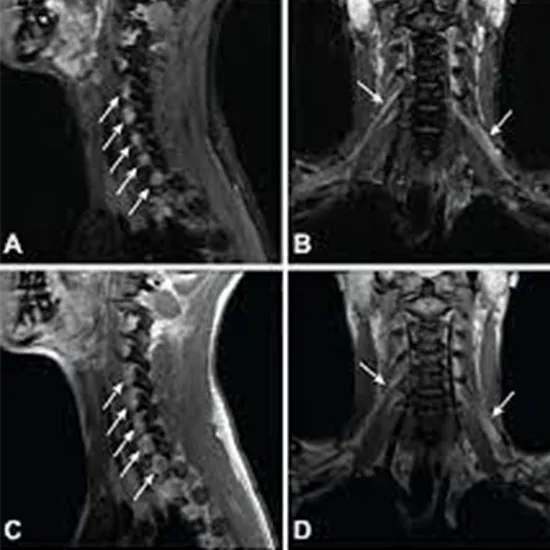

What is MRI Screening Brachial Plexus?

With an MRI of the Brachial Plexus, a picture of the nerve junction network (which gives nerves to the knee, thigh, abdomen, calves, back, and groin) and the soft tissues around it.